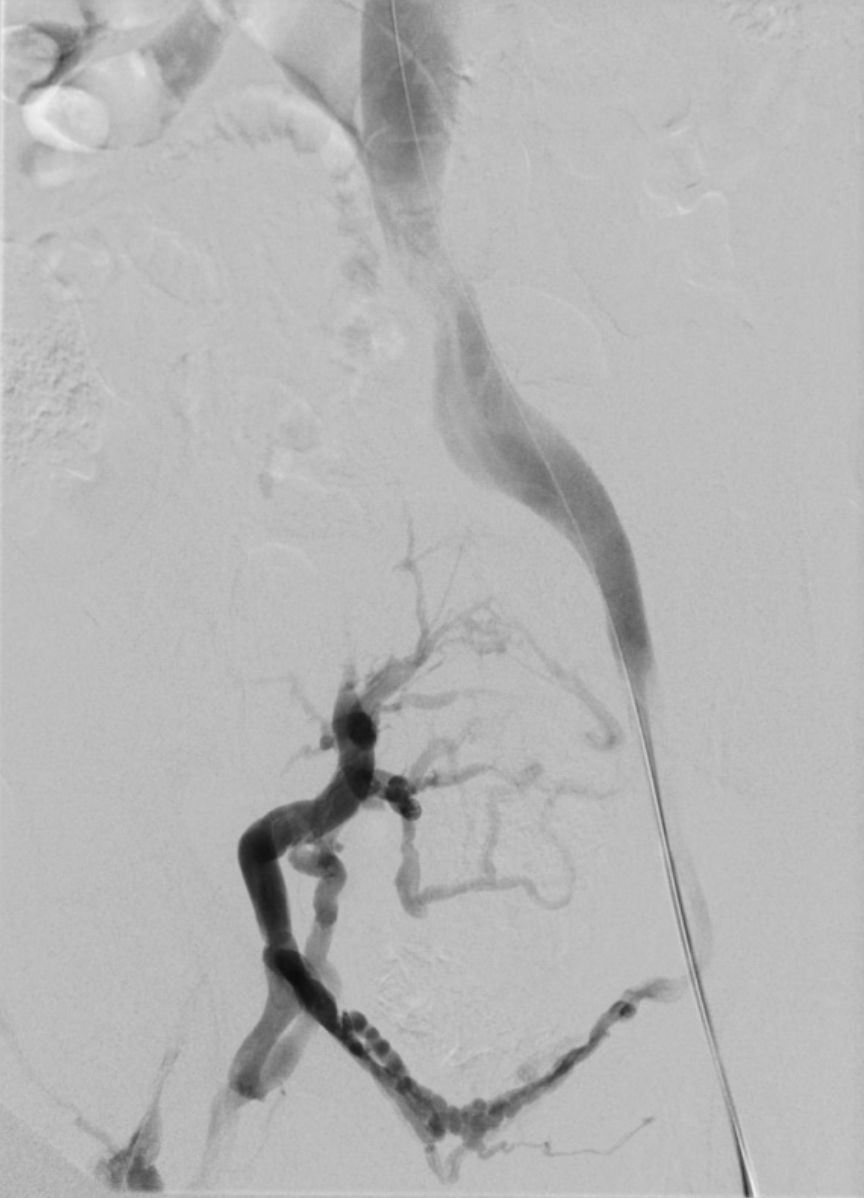

Rekanalisation mit Dilatation und Stents der rechtsseitigen Beckenvenen. Hierdurch wieder freier Fluss in den Beckenvenen.